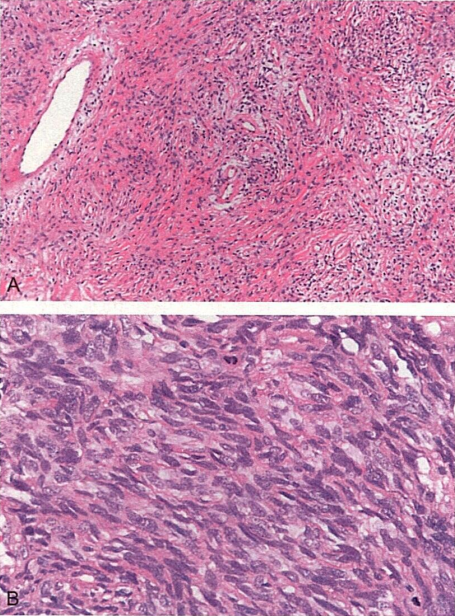

1.患者男,40岁。呼吸困难、胸痛、低血糖。术中见肿物位于脏层胸膜,单发,直径约5cm,境界清楚,质实,灰白。镜下观察见肿瘤细胞呈成纤维细胞样,细胞稀少区和细胞丰富区之间有粗的玻璃样变胶原和分支状血管分隔,富于细胞区呈席纹状排列,大部分异型性不明显。病理切片形态如图所示。

1.对该病例最可能的诊断是编辑

• A.纤维肉瘤

• B.血管周细胞瘤

• C.肉瘤样间皮瘤

• D.单相型滑膜肉瘤

• E.孤立性纤维性肿瘤;